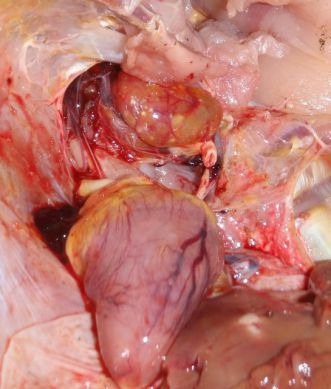

تشخیص

پرندگانی

که از آسیت می میرند بسیار ساده است. کافی است هنگام کالبد شکافی کمر پرنده باز شود در اینصورت مقدار قابل توجهی ماده خونی و یا ژله مانند از آن بیرون می ریزد گاهی اوقات پرندگان مبتلا به آسیت به دلیل اثرات ناشی از وجود مقادیر بسیار زیاد خون و جریان در شش هایشان می میرند قبل از اینکه مقدار قابل توجهی از جریان در حفره های بدن تشکیل شود